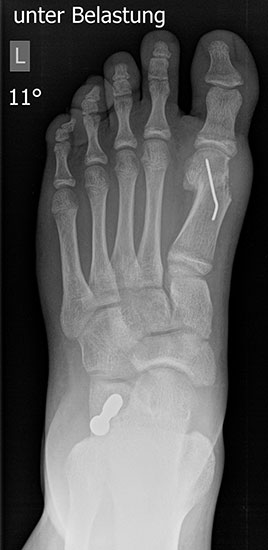

Röntgen

Standard ist die belastete Röntgenaufnahme des Fußes dorso-plantar und seitlich. Günstig ist eine Röhrenkippung von 10°-20°, um die Gelenke der Lisfranc-Linie einsehen zu können.

• Hallux valgus Winkel

• Hallux valgus interphalangeus Winkel

• Intermetatarsalwinkel I zu II

• Distaler Metatarsale Gelenkwinkel (PASA)

• Form des Mittelfußknochenkopfes

• Winkel Metatarsale I Basis zum Os cuneiforme mediale

• Metatarsalindex

• Elevation/ Plantarisierung I. Strahl

• Pes metatarsus adductus

• Wachstumsfugen

Tabelle 1: Normwerte der Winkelmaße

Intermetatarsalwinkel Hallux valgus Winkel

Normalwerte < 10° < 20°

Leichte –mittelgradige Fehlstellung 10°- 16° 20°- 40°

Schwere Fehlstellung > 16° > 40°